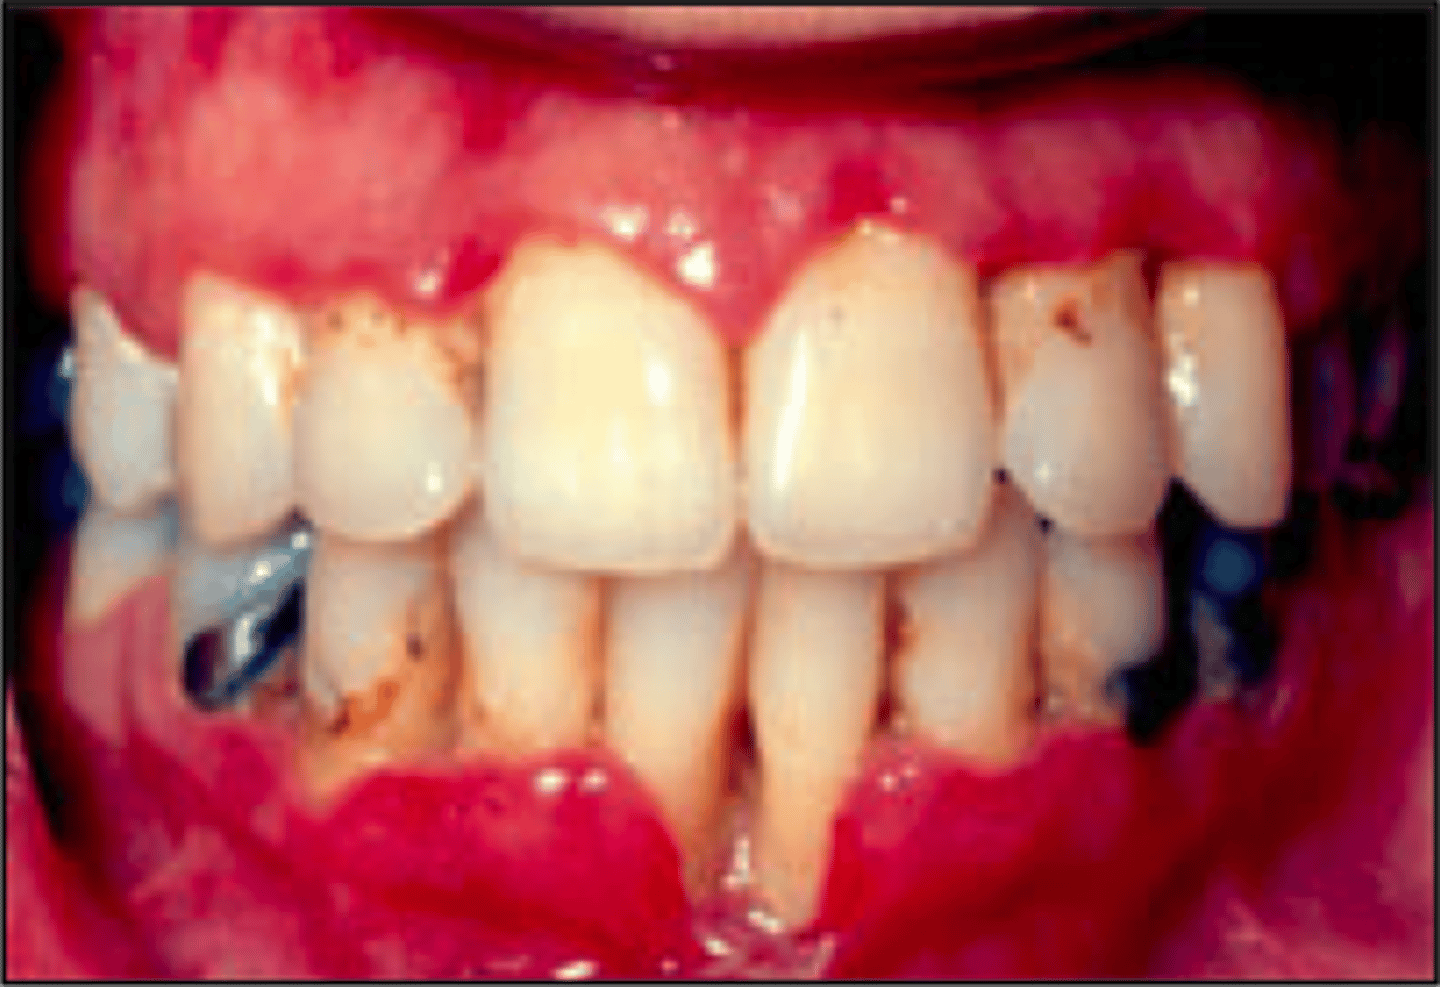

Necrotizing Ulcerative Gingivitis/Trench Mouth

Pathogen: 2 or more species of anaerobic bacteria

S+S: Painful bleeding of the gingivae, fever, swollen cervical lymph nodes, extreme halitosis

Prevention: Maintain good oral hygiene (not contagious)